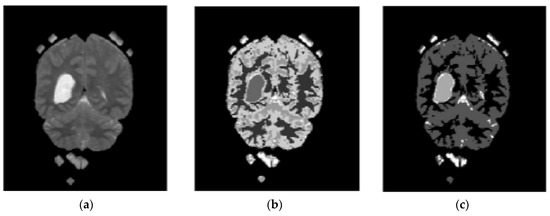

In the proposed segmentation approach, enhanced fuzzy c-means clustering is applied for brain tumor segmentation. In this method, an image’s N pixels are divided into fuzzy c clusters, where c is a positive number and n is a smaller number. Figure 4 and Figure 5 depict various sets of MRI brain images, such as the normal or original image, the binary level image, and the post-morphological operation outcome [37]. The segmentation process is taken as an enhanced version of the fuzzy c-means clustering (EFCMC) algorithm. This includes various stages, as shown in Figure 4 and Figure 5. After performing EFCMC, a final segmented tumor appeared. The proposed segmentation process took less time and was computationally less difficult than other methods.

An additional set of data was provided in the form of clusters. Alternately, we used a refined version of the fuzzy c-means clustering technique. It is useful for extracting features using LBGLCM and yields decent results when used with segmentation methods.

A total of 620 MRI scans of the brain were analyzed, 612 of which were deemed normal and 8 of which showed signs of tumor growth (abnormal). It took a few stages of the enhanced fuzzy c-means clustering method to get the area of the brain where the tumor was located. The upgraded fuzzy c-means clustering technique was assumed to be used in the segmentation process. There were several steps involved, as seen in Figure 4, Figure 5 and Figure 6. The tumor was successfully segmented after the EFCMC. The proposed segmentation method was faster and required fewer computer resources than other methods. Figure 6 illustrates the brain MRI images, such as the third stage of the enhanced fuzzy c-means cluster impact and it provides the outcome of the segmented tumor region.